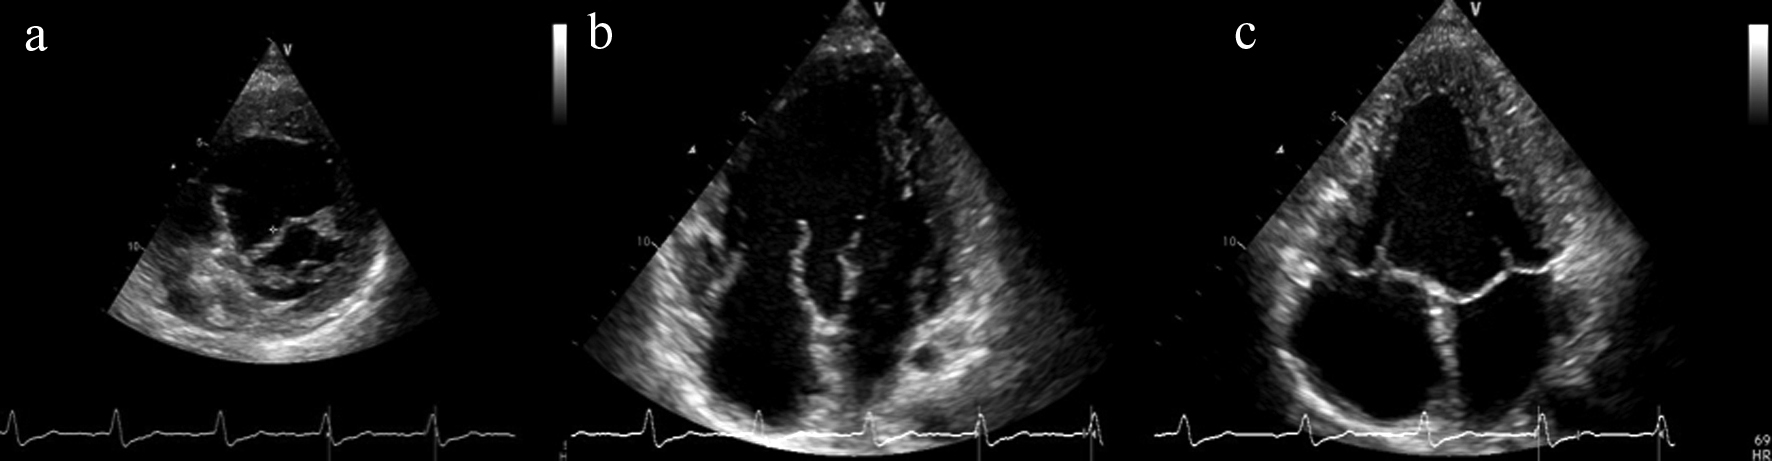

При ЭхоКГ (рис. 2) отмечалась митральная и трикуспидальная регургитация II–III степени, функционирующее овальное окно диаметром 4–5 мм, единственный двуприточный левый желудочек, фракция выброса левого желудочка – 75%.

Рис. 2. Данные эхокардиографии.

а – короткая парастернальная позиция на уровне митрального клапана; б – верхушечная 4-х камерная позиция, диастола; в – верхушечная 4-х камерная позиция, систола.